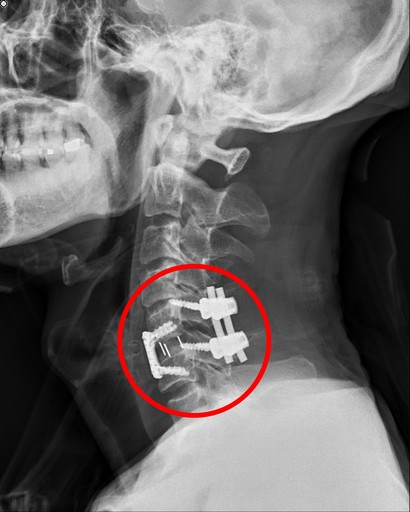

洪祥益主任五個小時內為宋先生進行三階段手術,一是先將頸椎骨折脫臼復位,接下來以顯微鏡清除壓迫到神經的破碎椎間盤和骨刺後再融合,最後在頸椎後方以四根釘子做後固定加強,等於頸椎前後做了三百六十度的固定融合手術。

花蓮慈濟醫院洪祥益主任為宋先生進行微創手術,加上頸椎骨折復位及後固定融合手術。